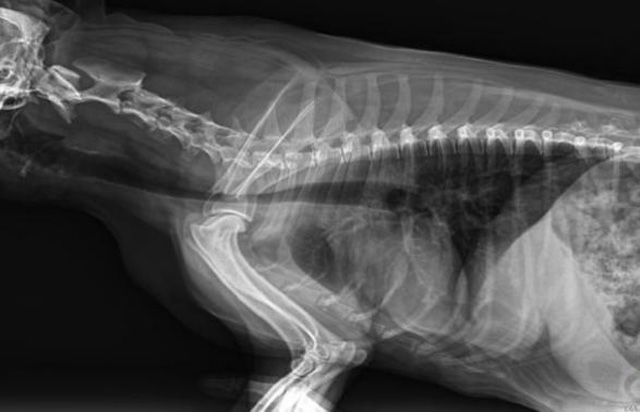

寵物DR是動物專用的數(shù)字化攝影系統(tǒng),x線的穿透能力、低的輻射劑量,輻射劑量比X光低:熒光作用和感光作用,可以穿透動物身體的結(jié)構(gòu)顯示成像,動物的各個部位成像輔助獸醫(yī)診療。寵物DR采集時間10ms以下,成像時間僅為3秒,從檢查到出診斷報告大約5—10分鐘。較高的空間分辨力和低噪聲率,可獲得高清晰圖像。 DR成像數(shù)字化處理的特點(diǎn)可進(jìn)行后處理。提高了病灶的檢出率,這樣大大提高檢查的準(zhǔn)確率提高診斷準(zhǔn)確率避免漏診誤診等情況。